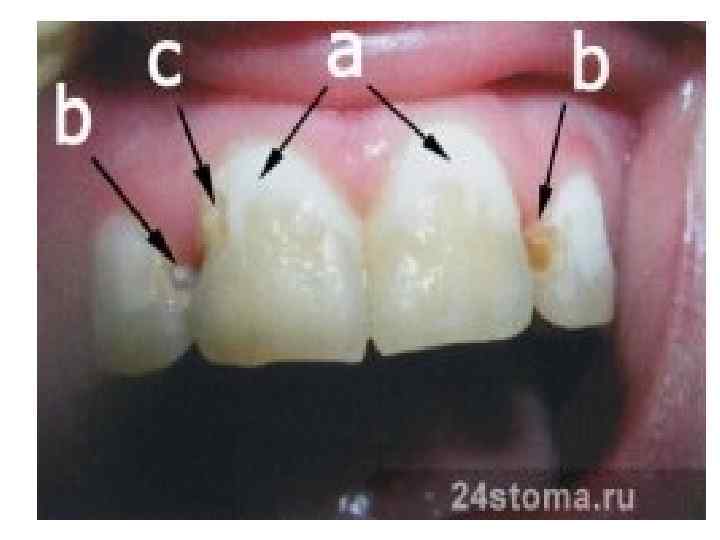

Цвет зуба • Зубы человека могут иметь различную окраску ― от молочно-белой до темно-коричневой. • Отмечают изменение цвета всей коронки или отдельных ее участков. • Зубы, лишенные пульпы, становятся тусклыми, принимают сероватый, иногда ― желтоватый оттенок в результате применения фармакологических препаратов. • При кариесе цвет зуба меняется соответственно степени выраженности патологического процесса ― исчезновение естественного блеска эмали, меловидное пятно, окрашивание кариозного пятна от серого до темнокоричневого тонов.

Изменение цвета зубов • Амальгамы окрашивают зуб в темный цвет. • При травме зуба, сопровождающейся поражением пульпы, цвет зуба становится розоватым и со временем темнеет. • Курение, а также применение различных красителей (крепкий чай, кофе) приводят к соответствующему изменению цвета зубов.

Изменение цвета эмали зуба, пломба из амальгамы